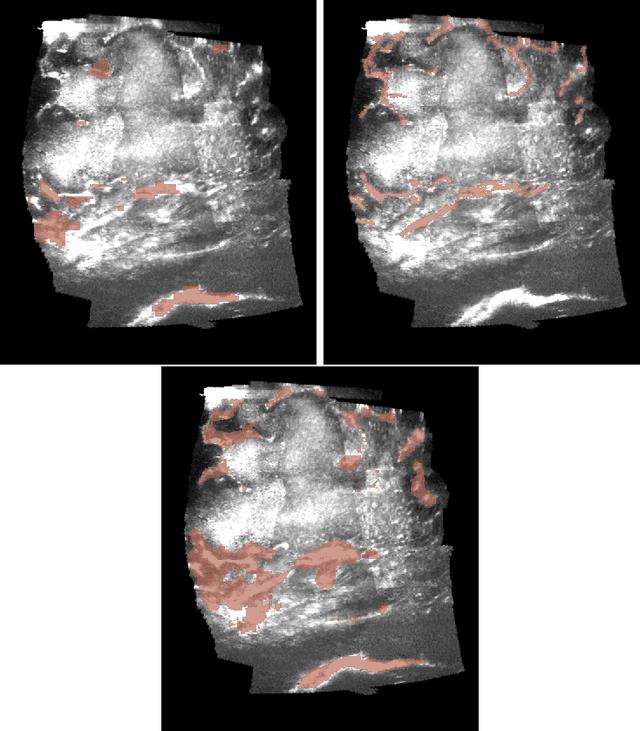

Abstract:Freehand three-dimensional ultrasound (3D-US) has gained considerable interest in research, but even today suffers from its high inter-operator variability in clinical practice. The high variability mainly arises from tracking inaccuracies as well as the directionality of the ultrasound data, being neglected in most of today's reconstruction methods. By providing a novel paradigm for the acquisition and reconstruction of tracked freehand 3D ultrasound, this work presents the concept of Computational Sonography (CS) to model the directionality of ultrasound information. CS preserves the directionality of the acquired data, and allows for its exploitation by computational algorithms. In this regard, we propose a set of mathematical models to represent 3D-US data, inspired by the physics of ultrasound imaging. We compare different models of Computational Sonography to classical scalar compounding for freehand acquisitions, providing both an improved preservation of US directionality as well as improved image quality in 3D. The novel concept is evaluated for a set of phantom datasets, as well as for in-vivo acquisitions of muscoloskeletal and vascular applications.